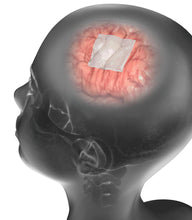

Nuestra membrana de reparación de duramadre original, fue diseñada para optimizar adaptabilidad y resistencia. Tiene un grosor similar a la de la duramadre natural y puede ser aplicada sobrepuesta o como una membrana suturable. Tiene balance efectivo en la reabsorción del tejido y reemplazo equilibrado.

DuraMatrix® tiene un tiempo de reabsorción de 26-38 semanas, comparado con las menos de 12 semanas de otras marcas en estudio de duraplastia en conejos. DuraMatrix® fue específicamente diseñada para ser reabsorbida a un ritmo balanceado que le da al tejido nativo suficiente tiempo para regenerarse